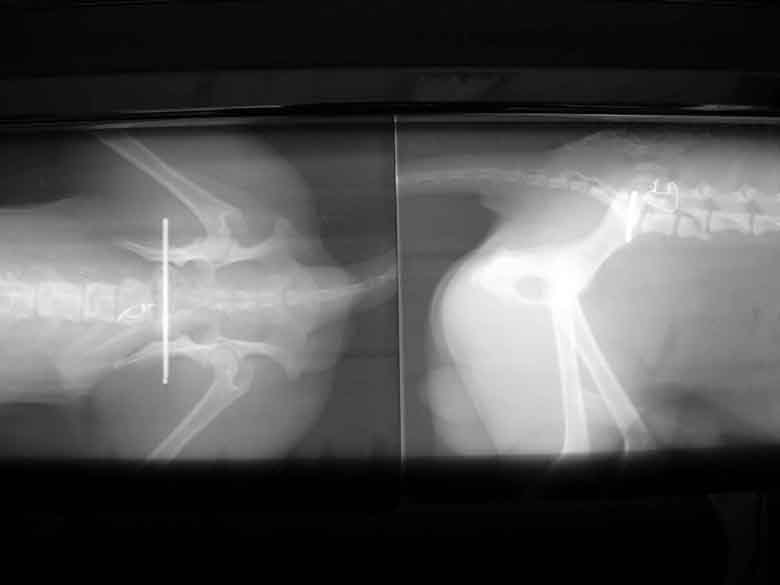

Beckenfaktur

Plattenrekonstruktion

Hüftgelenksluxation

Bohrdraht-Fixation